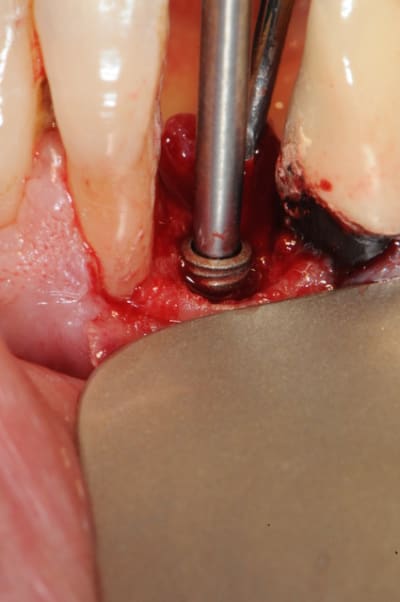

1) foret unique

2) taraudage (fortement recommandé)

3)4) packaging

5) vis de couverture transgingivale en pick

6) porte implant manuel

7)8) on met l'implant avec ses petits didis

9)10)11) implant in situ